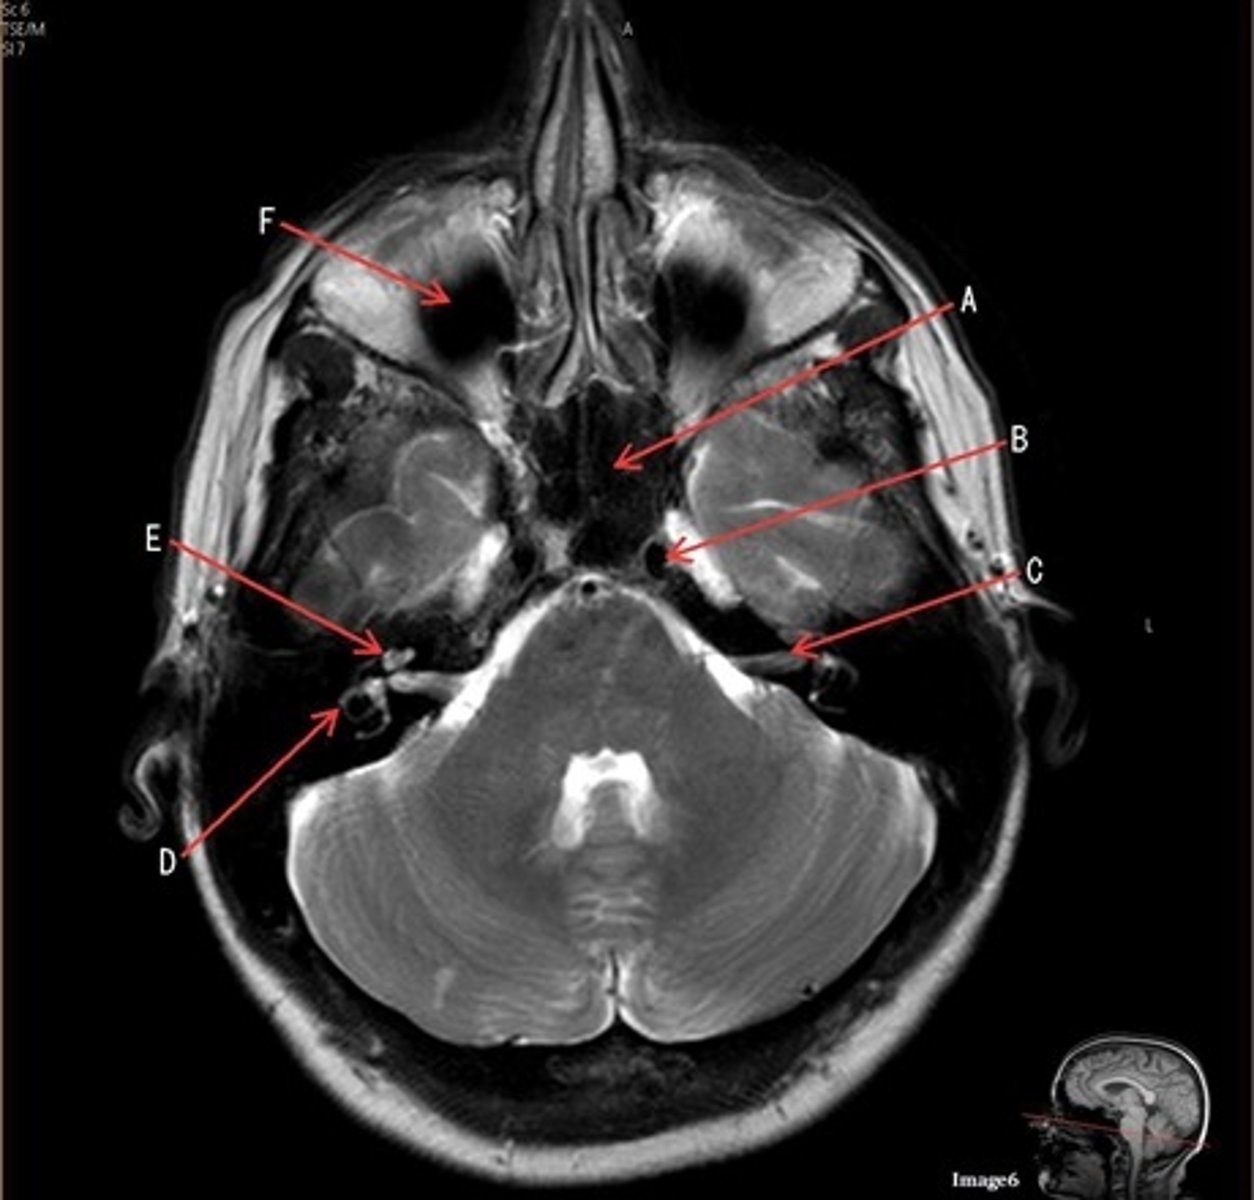

C

C- 7th cranial nerve, facial nerve

D

D. semi-circular canal

E

E- cochlea

F

F- maxillary sinus